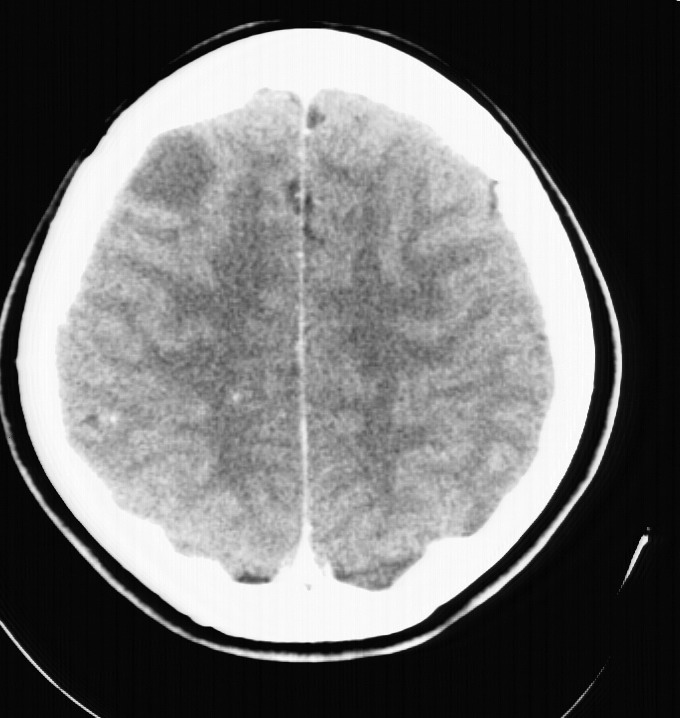

标题: CT5853:右额叶上部占位请会诊

女,34岁,自述头晕胀2年,近期感精神恍惚,无发热,实验室检查阴性。

强化后呈环状强化,支持1级星型细胞瘤可能.

右顶叶靠近脑表面圆形低密度灶,周围无水肿及占位效应,增强病灶无明显强化,考虑:右顶叶低分级星型细胞瘤。

右额叶上部皮质区见类圆形低密度区,边界不清,无强化,无钙化。

支持大多数战友的意见,1级星形细胞瘤。